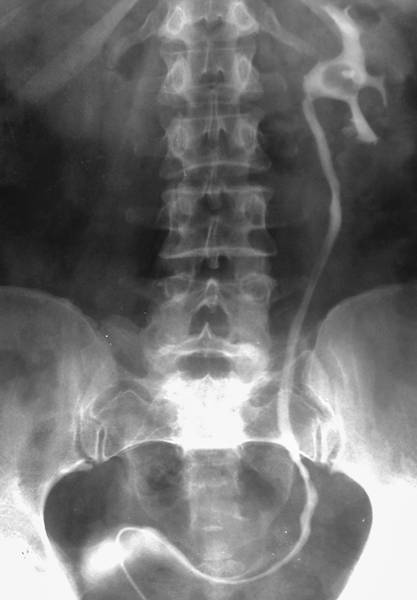

РЕТРОГРАДНАЯ УРЕТЕРОПИЕЛОГРАФИЯ

Ретроградная уретеропиелография впервые выполнена в 1906 г. Voelcker и Lichtenberg. Метод основан на получении теней ВМП после их ретроградного заполнения контрастным веществом (рис.).

Ретроградная уретеропиелограмма слева: тень мочеточникового катетера в проекции мочевого пузыря и нижней трети мочеточника; в лоханке — дефект наполнения округлой формы с ровными чёткими контурами, обусловленный рентгенонегативным камнем.

Для этого применяют жидкие (амидотризоевая кислота, йогексол) и газообразные (кислород, углекислый газ) контрастные вещества. По мочеточниковому катетеру вводят от 2 до 5 мл жидкого контрастного препарата. Если при этом у больного возникает боль или неприятные ощущения в области почки, то следует прекратить дальнейшее его введение и сделать рентгеновский снимок. Лучше проводить это исследование под рентгентелевизионным контролем. Ретроградную уретеропиелографию следует выполнять с одной стороны, а если есть показания, — то и с другой, но не одновременно. При макрогематурии ретроградную уретеропиелографию применять не рекомендовано, так как сгустки крови могут давать дефекты наполнения и быть ошибочно приняты за опухоль или конкремент.

В норме на уретеропиелограмме тень мочеточника располагается по латеральному краю поперечных отростков поясничных позвонков в виде тонкой полосы шириной 3–5 мм.